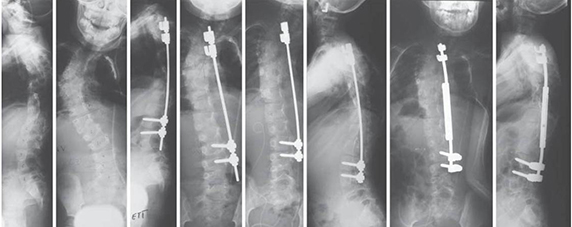

Műtét kisgyermekkorban

Csigolyafejlődési rendelenességHa a rendellenes csigolya, csigolyák már kisgyermekkorban gerincferdülést okoznak, elképzelhető, hogy a gerincsebész műtét mellett dönt. Ennek legkorábbi, egyúttal legjellemzőbb időpontja a gyermek 3-4 éves kora körül van. Nagyon fontos tudni, hogy ez - kisgyermekkorban végzett – operáció MEGELŐZŐ jellegű, tehát egy nagyobb görbület, súlyosabb állapot kialakulását szeretnék megakadályozni vele.

Jellemzői:

- relatív kis megterheléssel jár

- kevés implantátumot igénylő beavatkozás

- néhány napos kórházi befekvés szükséges

- rövid műtéti idő

- pár hét otthon lábadozás (nem szükséges gyógytorna, rehabilitáció)

- gyors felépülés

- mozgásban gazdag, teljes élet a műtétet követően

Az ún. open-wedge technikával történő műtét (dr. Jeszenszky nevéhez fűződő forradalmian új technika) a későbbiekben „nyújtásokat”, tehát további kisebb beavatkozásokat igényel.